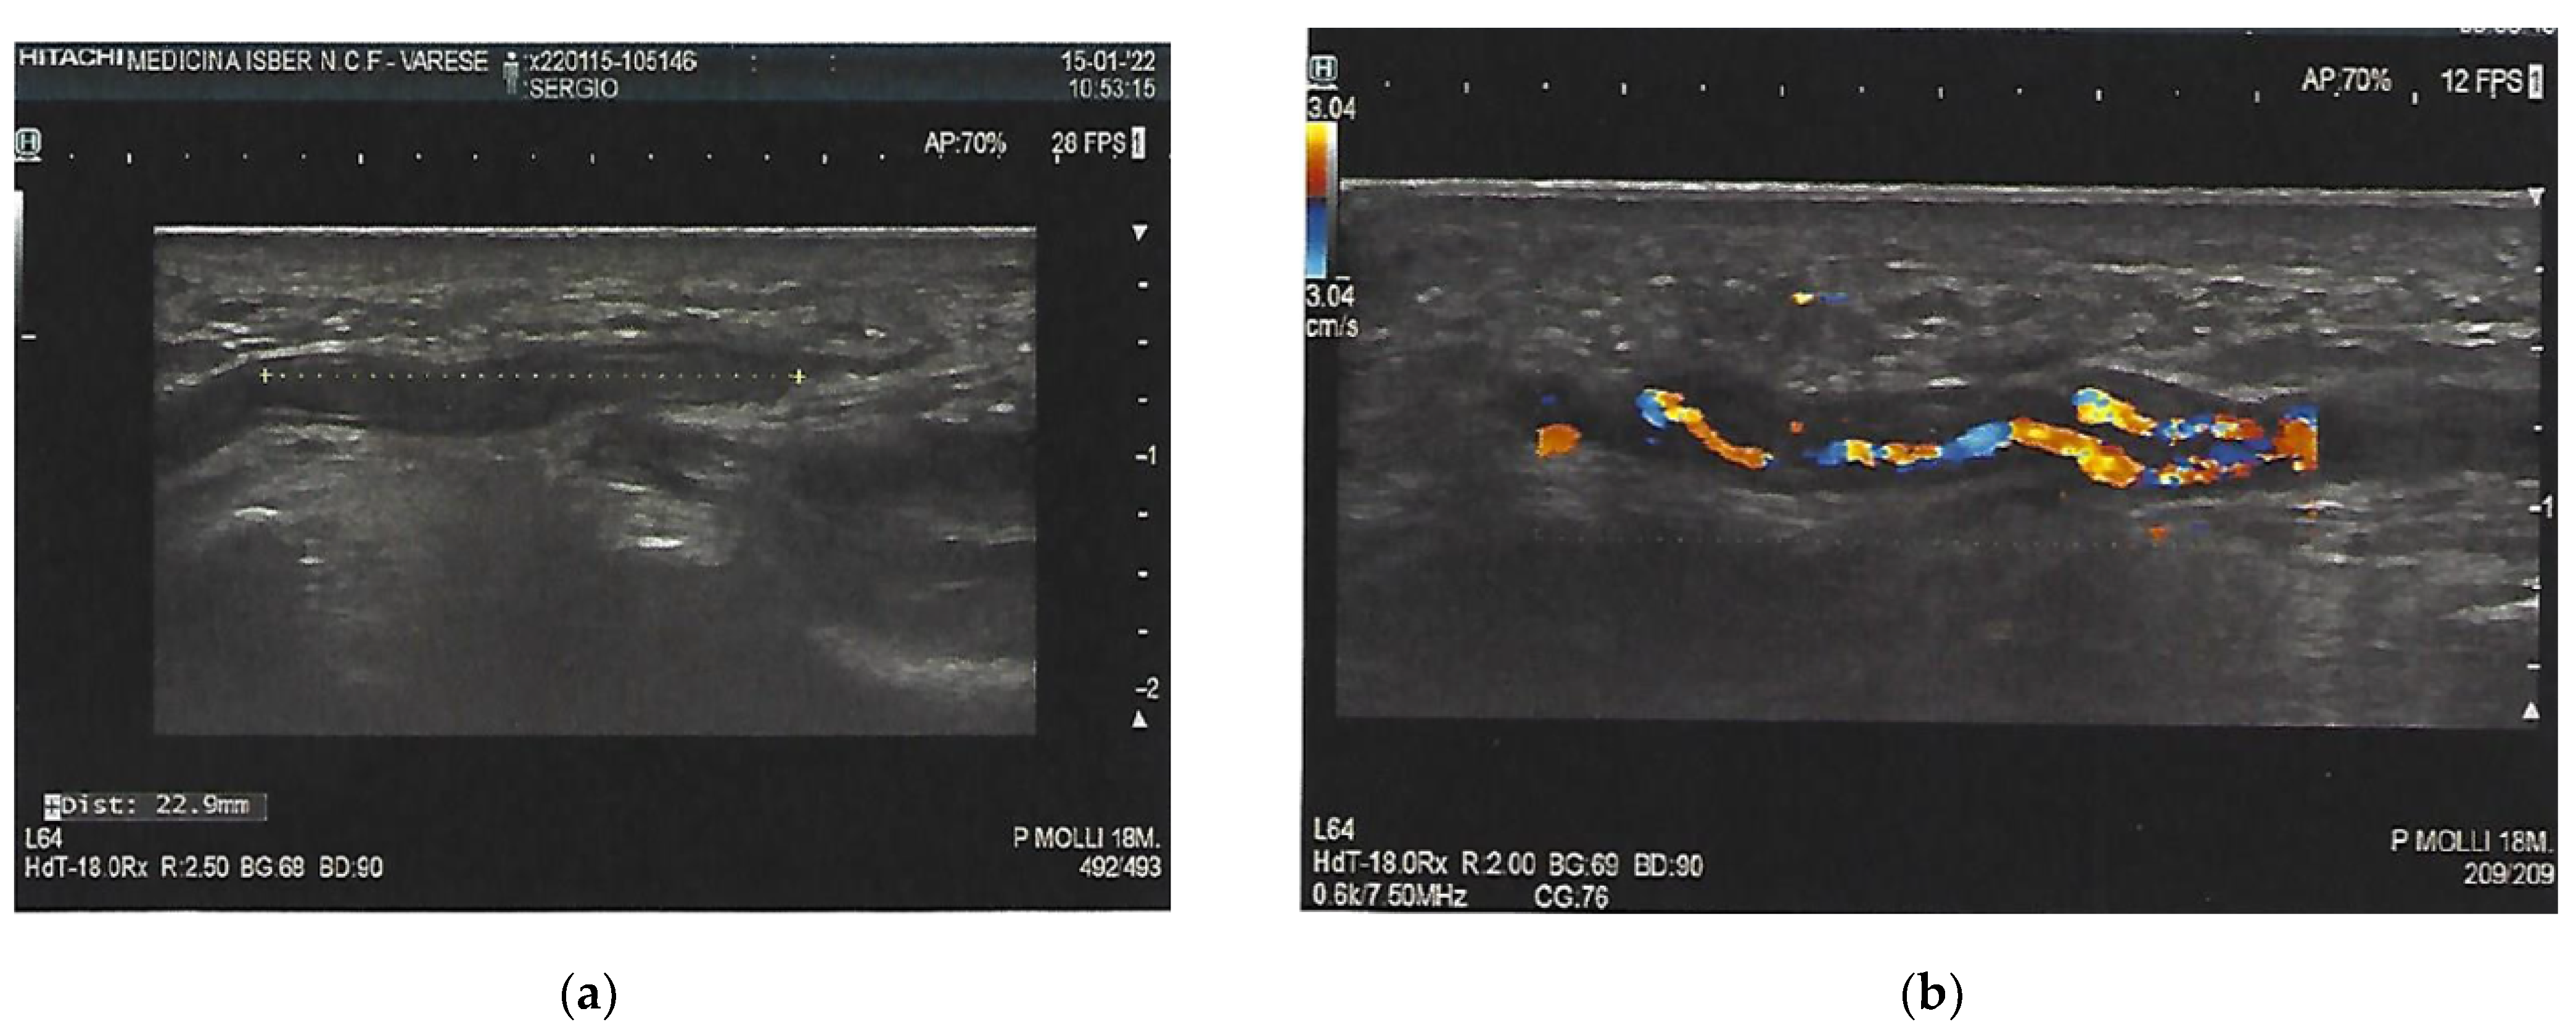

2. Case Presentation

3. Investigations